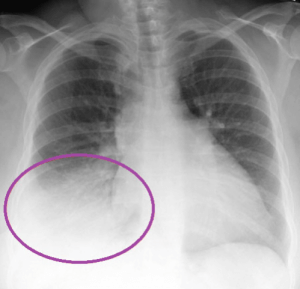

Признаки пневмонии на снимке

- Пневмония. Воспаление легких на рентгенограмме выявляется как инфильтративные затемнения и уменьшение прозрачности легочных полей. Как правило, врач диагностирует пневмонию безошибочно.